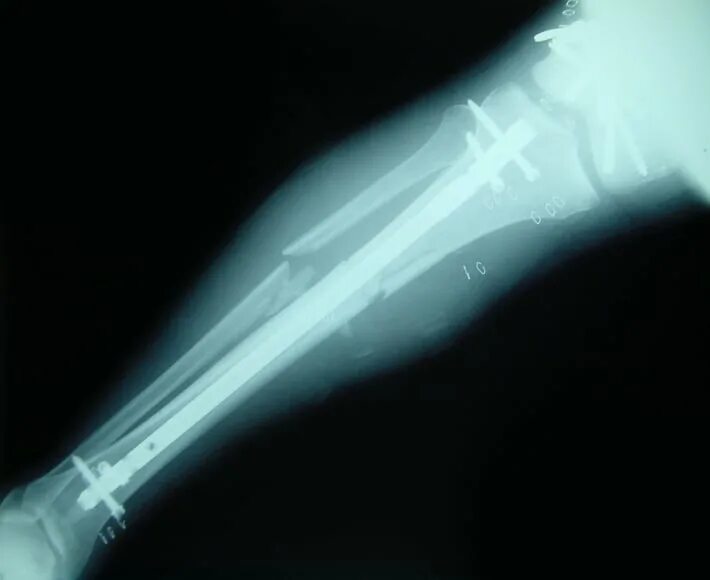

Перелом берцовых